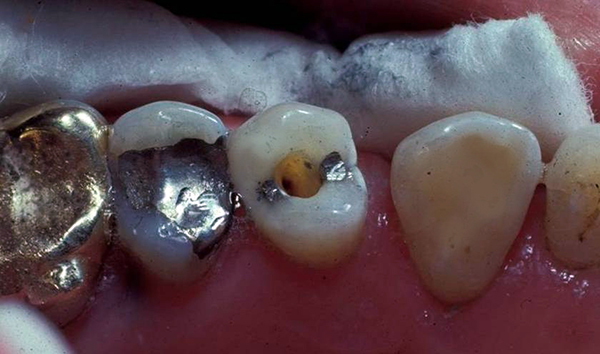

Fig 15. The first premolar has intact marginal ridges bilaterally and may be restored with a direct resin as the final restoration after endodontic treatment, but the second premolar if treated endodontically would require a post to retain a core and a full-coverage crown due to the amount of missing native tooth structure.

Figure 15